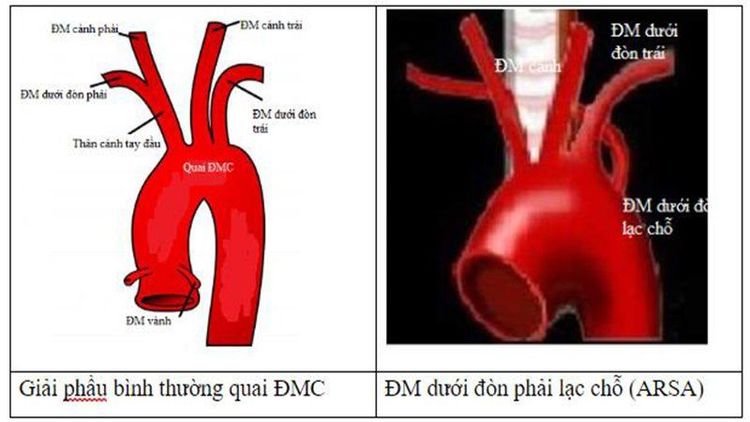

ARSA là từ viết tắt của Aberrant Right Subclavian Artery bản chất là động mạch dưới đòn phải lạc chỗ. ARSA là một biến dạng tương đối thường gặp của các nhánh của quai động mạch chủ. Động mạch chủ là một trong những mạch máu lớn vận chuyển máu từ tim đi: nó cung cấp máu giàu oxy tới đầu và thân mình.

Động mạch chủ đi ra khỏi tim, nó chạy hướng lên phía đầu, sau đó tạo nên quai động mạch chủ sau đó chạy xuống ngực và bụng. Ở hầu hết mọi người có 3 nhánh mạch máu của quai động mạch chủ đi hướng lên phía đầu, cổ và cánh tay.

Thông thường, động mạch dưới đòn phải xuất phát từ động mạch thân cánh tay đầu, là một nhánh của quai động mạch chủ. Khoảng 1% số người, quai động mạch chủ có 4 nhánh, và động mạch dưới đòn phải xuất phát trực tiếp từ động mạch chủ khi nó đi xuống ngực bụng. Nó chạy ra sau khí quản và thực quản (ống nối giữa miệng và dạ dày), và sau đó đi về phía vai và cánh tay phải. Hình dưới đây cho thấy quai động mạch chủ có 4 nhánh: động mạch cảnh chung phải, động mạch cảnh chung trái, động mạch dưới đòn trái và động mạch dưới đòn phải lạc chỗ (ARSA).

Trong thời kỳ phôi thai (những tuần đầu tiên trong tử cung), khi giải phẫu phức tạp của tim và các mạch máu đang phát triển, một số mạch máu bắt đầu thành cặp, hợp nhất, trong khi những mạch máu khác biến mất. Trong ARSA, mô hình phát triển thông thường có chút biến đổi, ngăn chặn việc sự hình thành bình thường của 3 nhánh mạch máu. Điều này dẫn đến có 4 nhánh chứ không phải 3 xuất phát từ cung động mạch chủ trái, một trong số đó là ARSA.